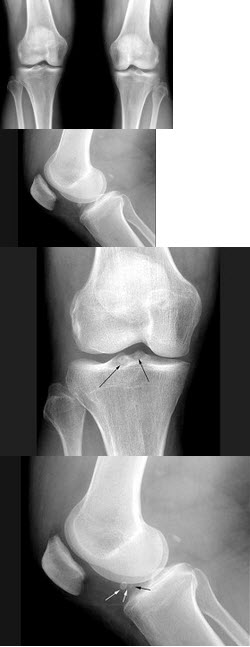

A.十二指肠球部溃疡

A.腺癌